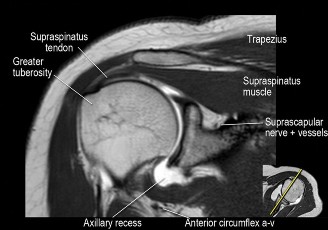

The correct answer is (B). An MRI showing a rotator cuff tear is considered diagnostic of a rotator cuff tear because of its high sensitivity, specificity, and accuracy. It has superb soft tissue imaging abilities (see Fig. 2–5). However, it should be noted that while MRI usually can differentiate between partial- and full-thickness rotator cuff tears, this varies with the power and accuracy of the MRI facility. This is also true with the ability of MRI to differentiate between partial-thickness rotator cuff tears and subacromial bursitis. An arthroscopy is needed for definitive differentiation of these pathologies.

Figure 2–5_Coronal oblique view MRI slice of a left shoulder. (Reproduced with permission from Smithius R and van de Woude HJ. Shoulder MR Anatomy: Normal Anatomy, Variants, and Checklist. _Radiology Assistant. April 2, 2012.)

Shoulder CT scans (Answer A) are not typically used to diagnose rotator cuff tears. X-rays, aka roentgenograms (Answer C), can show signs of rotator cuff pathology but are not diagnostic. Some signs of chronic rotator cuff tears that are sometimes seen on AP view x-rays include calcific tendonitis, calcification of the coracohumeral ligament, proximal migration of the humerus, and cystic changes of the greater tuberosity. An outlet view x-ray can show a type III (hooked) acromion, which is correlated with a higher rate of rotator cuff tears, or an OS acromiale, which would require special consideration for surgical treatment. Shoulder arthrograms (Answer D) are used primarily only when MRI is contraindicated and are considered positive for a rotator cuff tear if dye leaks from the glenohumeral joint into the subacromial space. MR arthrogram (Answer E) has been shown to have equivalent diagnostic ability compared with standard MRI and can be used to diagnose rotator cuff tears. However, it adds an additional step and cost to a standard MRI, and it does not offer any additional diagnostic benefit for rotator cuff pathology. Therefore, standard MRI is preferred to MR arthrogram.